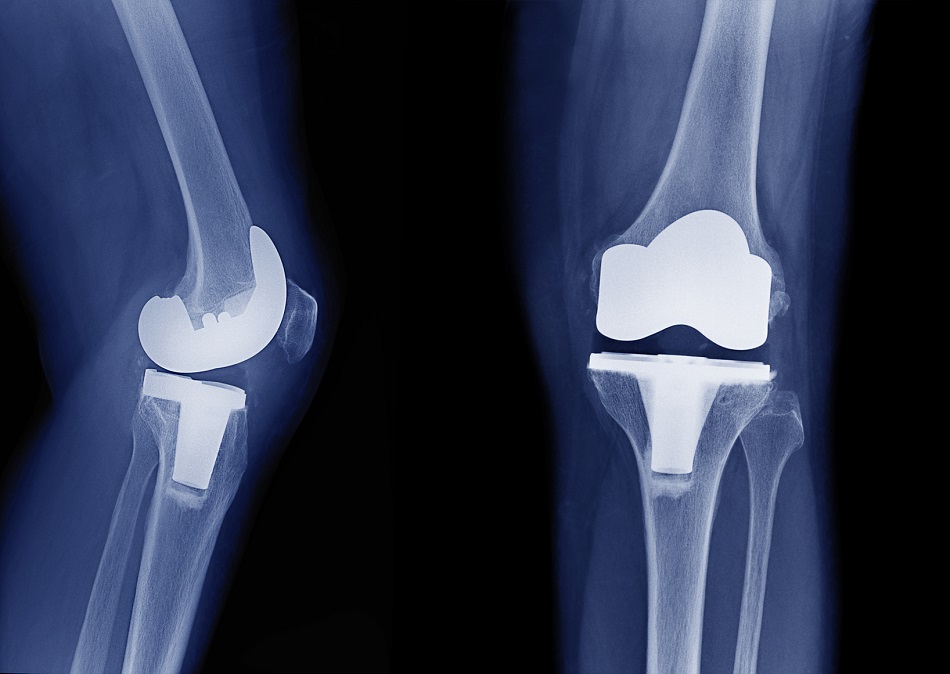

Discrepancia de miembros inferiores en artroplastia total de rodilla. ¿Es realmente un problema?

La incidencia de discrepancia de longitud de miembro inferior tras el con reemplazo total de rodilla fue del 30%. No se requirió intervención como consecuencia de dicha discrepancia. Los resultados funcionales y dolor al seguimiento alejado no demostraron diferencias entre ambos grupos. Rev Fac Cien Med Univ Nac Cordoba , 16 de septiembre de 2022